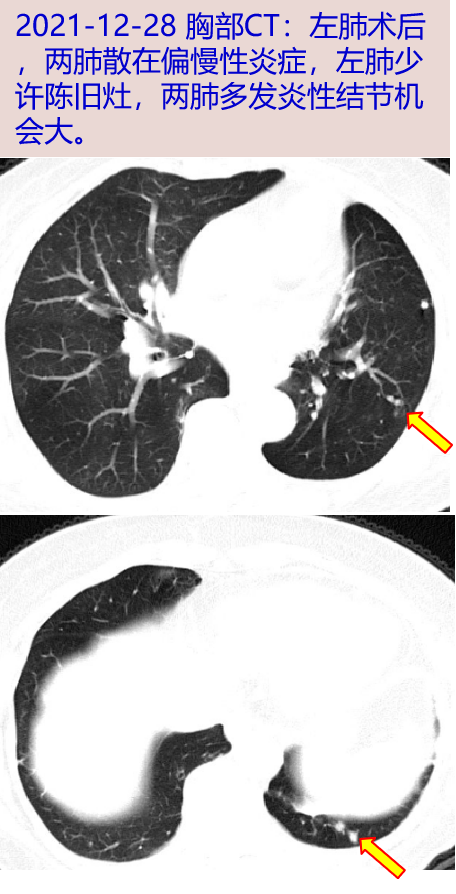

- 2021-12-28 胸部CT:左肺术后 , 两肺散在偏慢性炎症 , 左肺少许陈旧灶 , 两肺多发炎性结节机会大 。